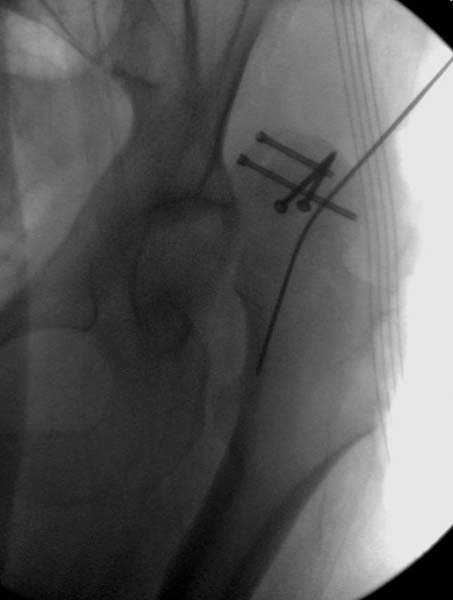

> Больная стабильная после хирургических мероприятии и получив добро,

> приступили к закрытому вправлению таранной кости с укладкой наружного

> фиксатора. Затем укладка больную на бок и открытый остеосинтез

> Остеосинтез бедра не стали делать из-за множественных переломов ребер с

> ушибом грудной клетки и поэтом у закончили фиксацию бедра наружным

> фиксатором.